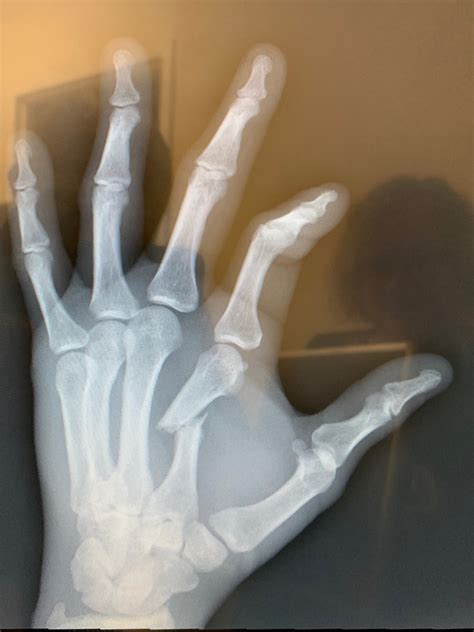

A broken hand x-ray is a type of medical imaging that uses low levels of radiation to produce images of the bones in the hand. These images are crucial for diagnosing fractures, dislocations, and other bone-related injuries. The x-ray machine emits X-rays that pass through the body and are absorbed differently by various tissues. Bones, being denser, absorb more X-rays and appear white on the resulting image, while softer tissues appear darker.

Hand fractures can occur in various bones and in different ways. Some of the most common types include:

• Metacarpal Fractures: These occur in the long bones of the hand, known as metacarpals. They are often caused by direct trauma, such as a punch or a fall.

• Phalangeal Fractures: These affect the bones of the fingers and thumb. They can be caused by crushing injuries, jamming, or twisting.